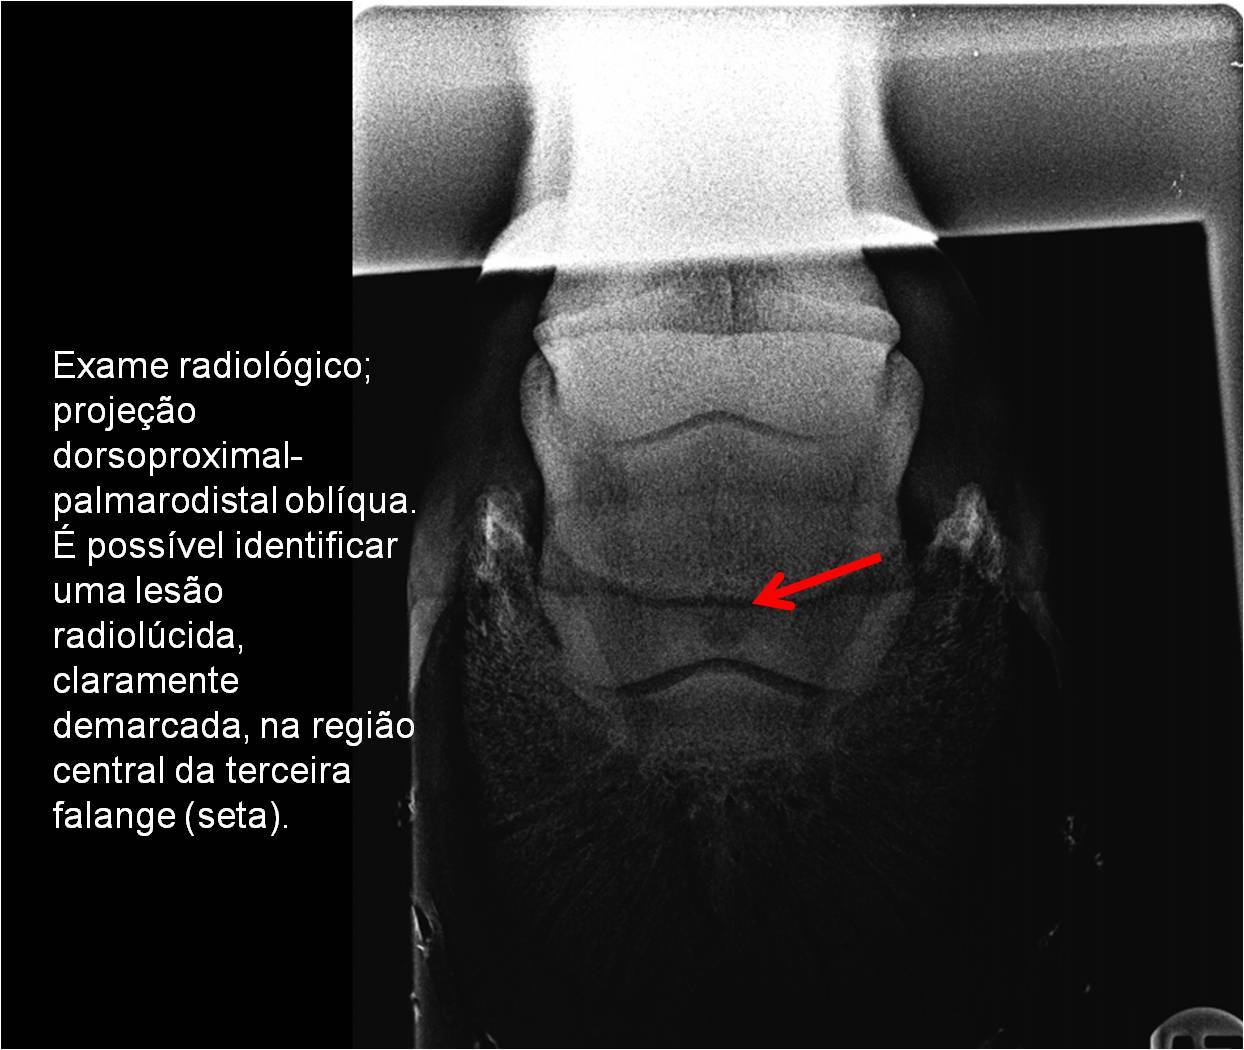

Publisher: Universidade de Évora

Abstract: O relatório de estágio encontra-se estruturado em três partes distintas. A primeira parte faz a caracterização das infraestruturas e funcionamento do Hospital Veterinário de Equinos de Lüsche, Oldenburg, Alemanha, assim como a análise casuística dos casos clínicos acompanhados durante os 6 meses de estágio. A segunda parte consiste de uma revisão bibliográfica sobre quistos do osso subcondral em equinos. Por fim, a terceira parte consta da apresentação e discussão de um caso clínico, nomeadamente o diagnóstico e acompanhamento imagiológico, por ressonância magnética, de um quisto subcondral na terceira falange num cavalo adulto; ### Abstract Equine Practice- Subcondral bone cyst of the third phalanx This internship report is divided in three parts. The first part characterizes the infrastructure and function of the Equine Hospital Lüsche, Oldenburg, Germany, as well as the casuistic of the clinical cases accompanied during the 6 month internship. The second part consists in a bibliographic review of cystic lesions of the subchondral bone in equines. The third part consists in a case report, the diagnostic and imagiological accompaniment, by use of magnetic resonance imaging, of a subchondral bone cyst in the distal phalanx of an adult equine.